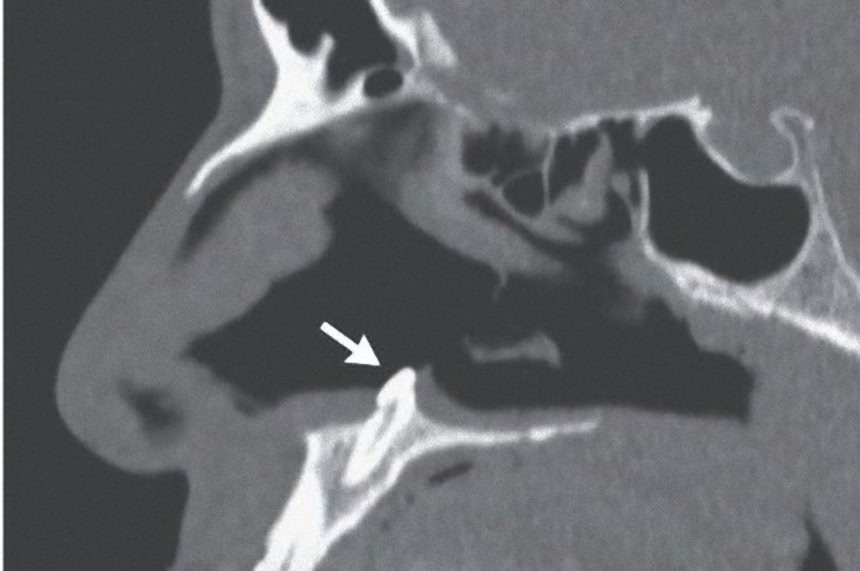

鼻の内部に生えた歯

ニューヨークのマウントサイナイ・ヘルスシステム(Mount Sinai Health System)で外科医を務めるマイケル・ターナー氏とサガル・カンナ氏が『New England Journal of Medicine』に症例報告したところによると、38歳の男性は「数年前から右の鼻の穴で呼吸がしづらい」として病院を訪れたという。

そこで医師らが確認したところ、鼻腔の間の仕切りが片側に押されている状態だったため、小型カメラで行った鼻鏡検査を行った。

その結果、右の鼻の孔の下側から白っぽい塊が出ていることが判明。実はこれ、成長した歯が生えていたのだ。

この画像を大きなサイズで見る突き出た歯の長さは約0.6cmほどに達しており、抜歯手術が行われた。取り除かれた歯は全長1.4cmあったそうだが、術後3ヶ月の経過観察では、両方の鼻の穴から普通に呼吸ができるようになったという。

本来生えてくる位置とは違った位置に歯が生えてくることはわりとあり、「異所萌出」と呼ばれているが、鼻の中から生えてくるケースは珍しい。